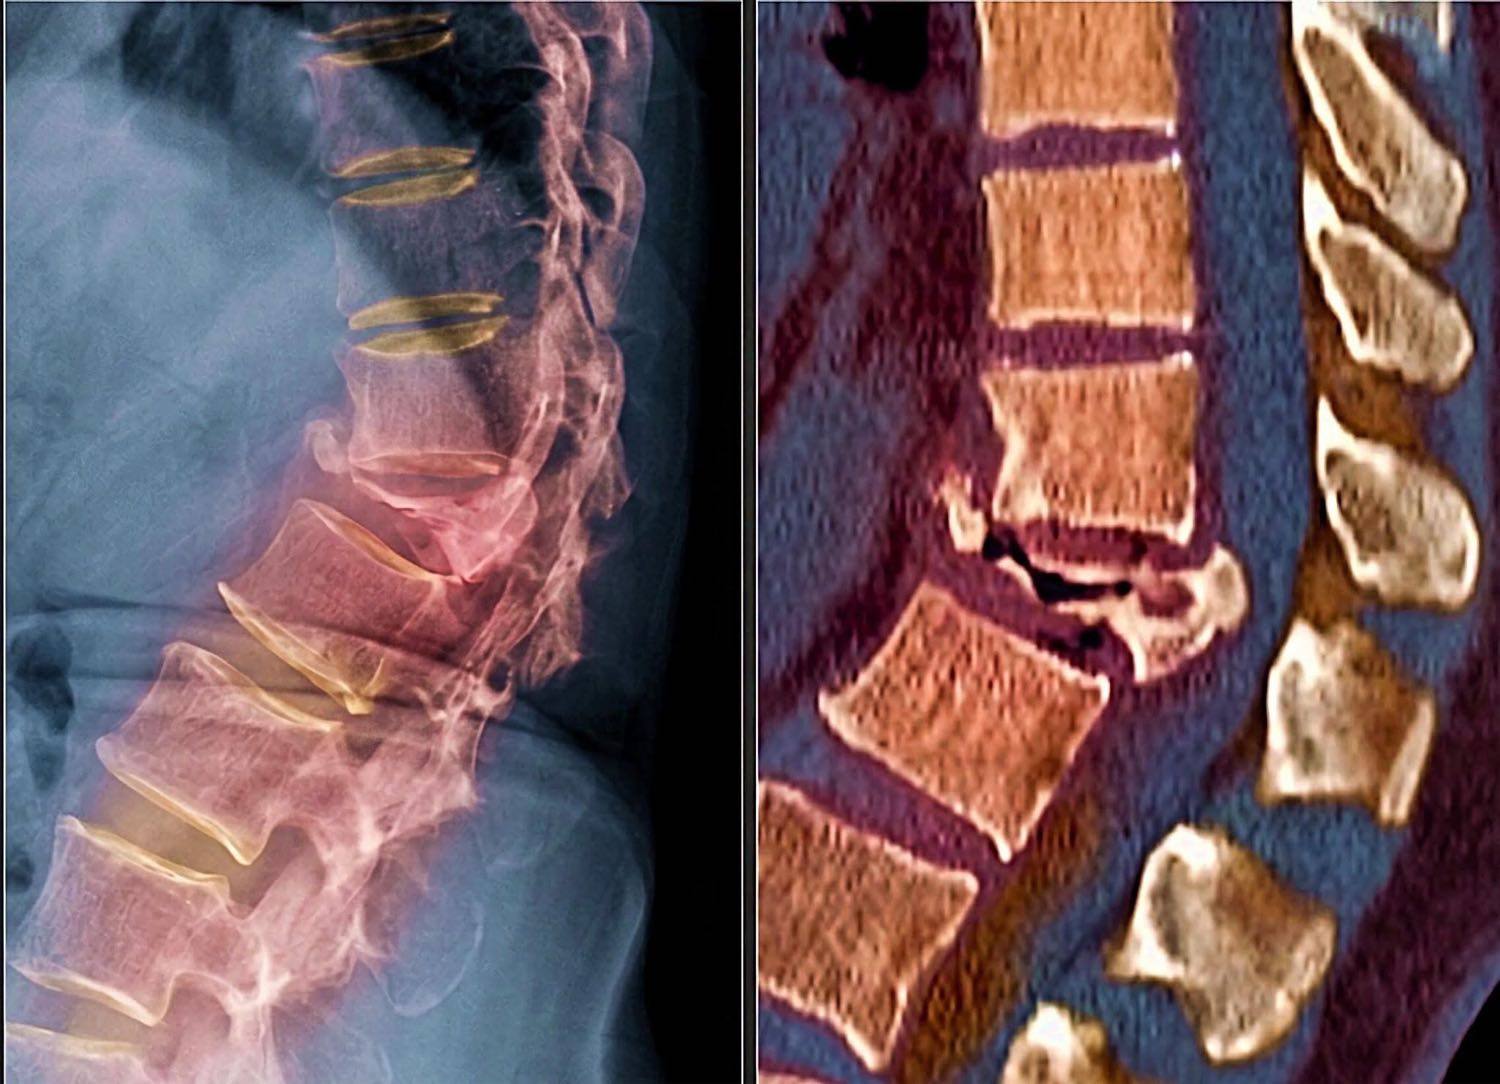

ภาพที่เห็นนี้คือ กระดูกสันหลังที่ยุบและหักจากภาวะกระดูกพรุน (osteoporosis)

ซึ่งน่ากลัวตรงที่

👉 ไม่ได้เกิดจากอุบัติเหตุรุนแรง

👉 แค่ล้มเบาๆ บิดตัว หรือแม้แต่ยกของธรรมดา

กระดูกก็สามารถหักยุบได้แล้ว

เมื่อมวลกระดูกลดลง โครงสร้างภายในกระดูกจะโปร่งเหมือนฟองน้ำ รับแรงได้น้อยลงมาก

กระดูกสันหลังจึงเป็นตำแหน่งที่ “พังง่าย” และทำให้เกิดอาการปวดหลังเรื้อรัง หลังค่อม ตัวเตี้ยลง หรือเดินลำบากตามมาได้